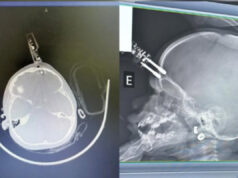

Menina que teve carregador de celular cravado na testa recebe alta